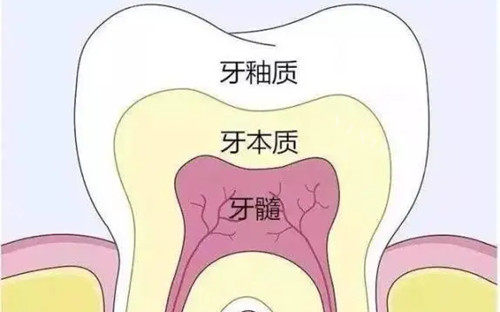

科室业务范围涵盖牙体牙髓病、牙周病、口腔黏膜病、口腔颌面外科、口腔预防、儿童口腔、口腔修复、口腔正畸、口腔种植科等。在意运用中西结合方法治疗口腔疾病,如牙周病、粘膜病等,颇具特色。